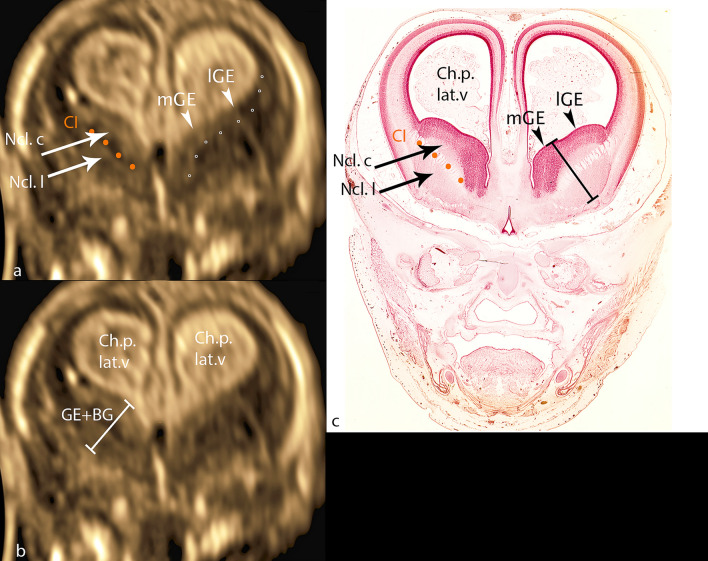

In the coronary section with marker dot in the choroid plexus 3.v, the typical hyperechogenic figure of the choroid plexus in the lateral ventricle can be visualized, while in the midline, also hyperechogenic, the interhemispheric fissure can be well visualized, followed laterally by a narrow hypoechogenic zone representing the cerebral wall (Fig. 2a). Caudal to choroid plexus, frequently just below, and sometimes separated by a narrow gap of cerebral liquor, ganglionic eminences bulge prominently into the anterior horn of the lateral ventricle. The most cranially protruding point is part of medial GE, a clear separation based on different echogenicity from lateral GE not being possible. Ganglionic eminences present with median echogenicity covering the basal ganglia cap-shaped cranially, laterally narrowing towards the cerebral wall, merging into it. Medially, its boundary, corresponding to the lateral edge of the medial cerebral mantle, is difficult to delineate on ultrasound. The basal ganglia situated below GE show an elliptic figure with its caudal surface adjacent to the hypoechoic cerebral wall lying below. As a final detail, the traversing fibers of the internal capsule can be visualized, separating nucleus caudatus from nucleus lentiformis (putamen). To verify all the details described, the corresponding histological section is added using analogous annotation (Fig. 2c).

Fig. 2.

CRL 71.1 mm a, b coronar plane c histologic specimen (CRL 73 mm): mGE—medial ganglionic eminence; lGE—lateral ganglionic eminence; dotted line (rings)—caudal border of GE; CI—capsula interna; orange line CI—fibers of capsula interna; Ncl.c—nucleus caudatus; Ncl. l—nucleus lentiformis; GE + BG—distance ganglionic eminence + basal ganglia

In the transcaudate coronary plane an oblique measurement of GE and BG was made at right angles to the fibers of capsual interna, starting with the point of GE that bulges most medially into the ventricle and ending with BG at its border with the cerebral wall (Fig. 2b).